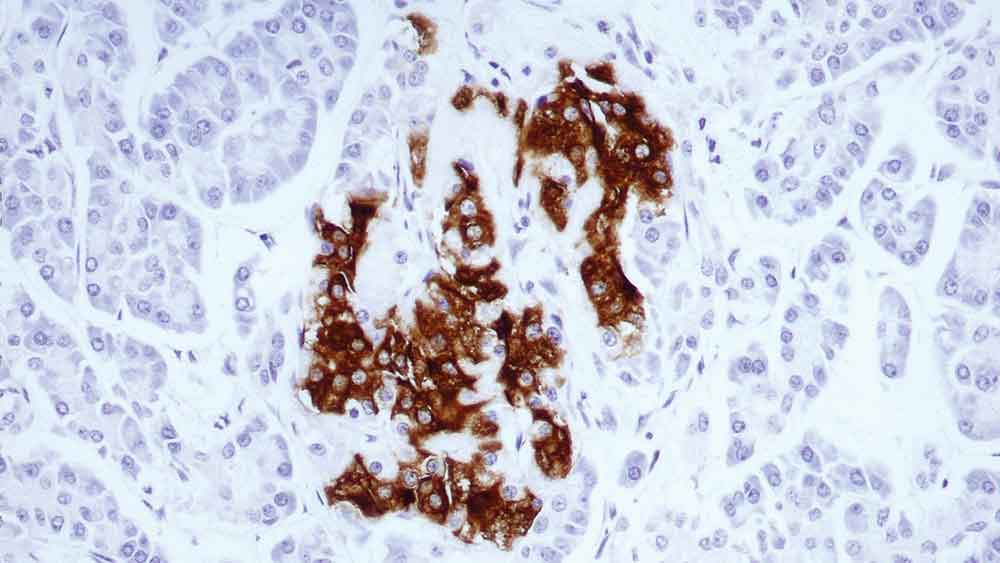

Squamous Cell Carcinoma of tonsil, stained with p16 BOND Ready-to-Use Primary Antibody (6H12), PA0016

p16 (INK4a) (Cyclin-dependent kinase inhibitor 2A (CDKN2A)) is a tumour suppressor protein associated with cell cycle progression, specifically in the regulation of transition from G1 phase of the cell cycle into the S phase. Oncogenic mutations in the CDKN2A gene that encodes p16 (resulting in over or under-expression of the protein) is associated with a wide range of cancers and cancer precursor lesions.

p16 is recommended for the detection of specific antigens of interest in normal and neoplastic tissues, as an adjunct to conventional histopathology using non-immunologic histochemical stains.